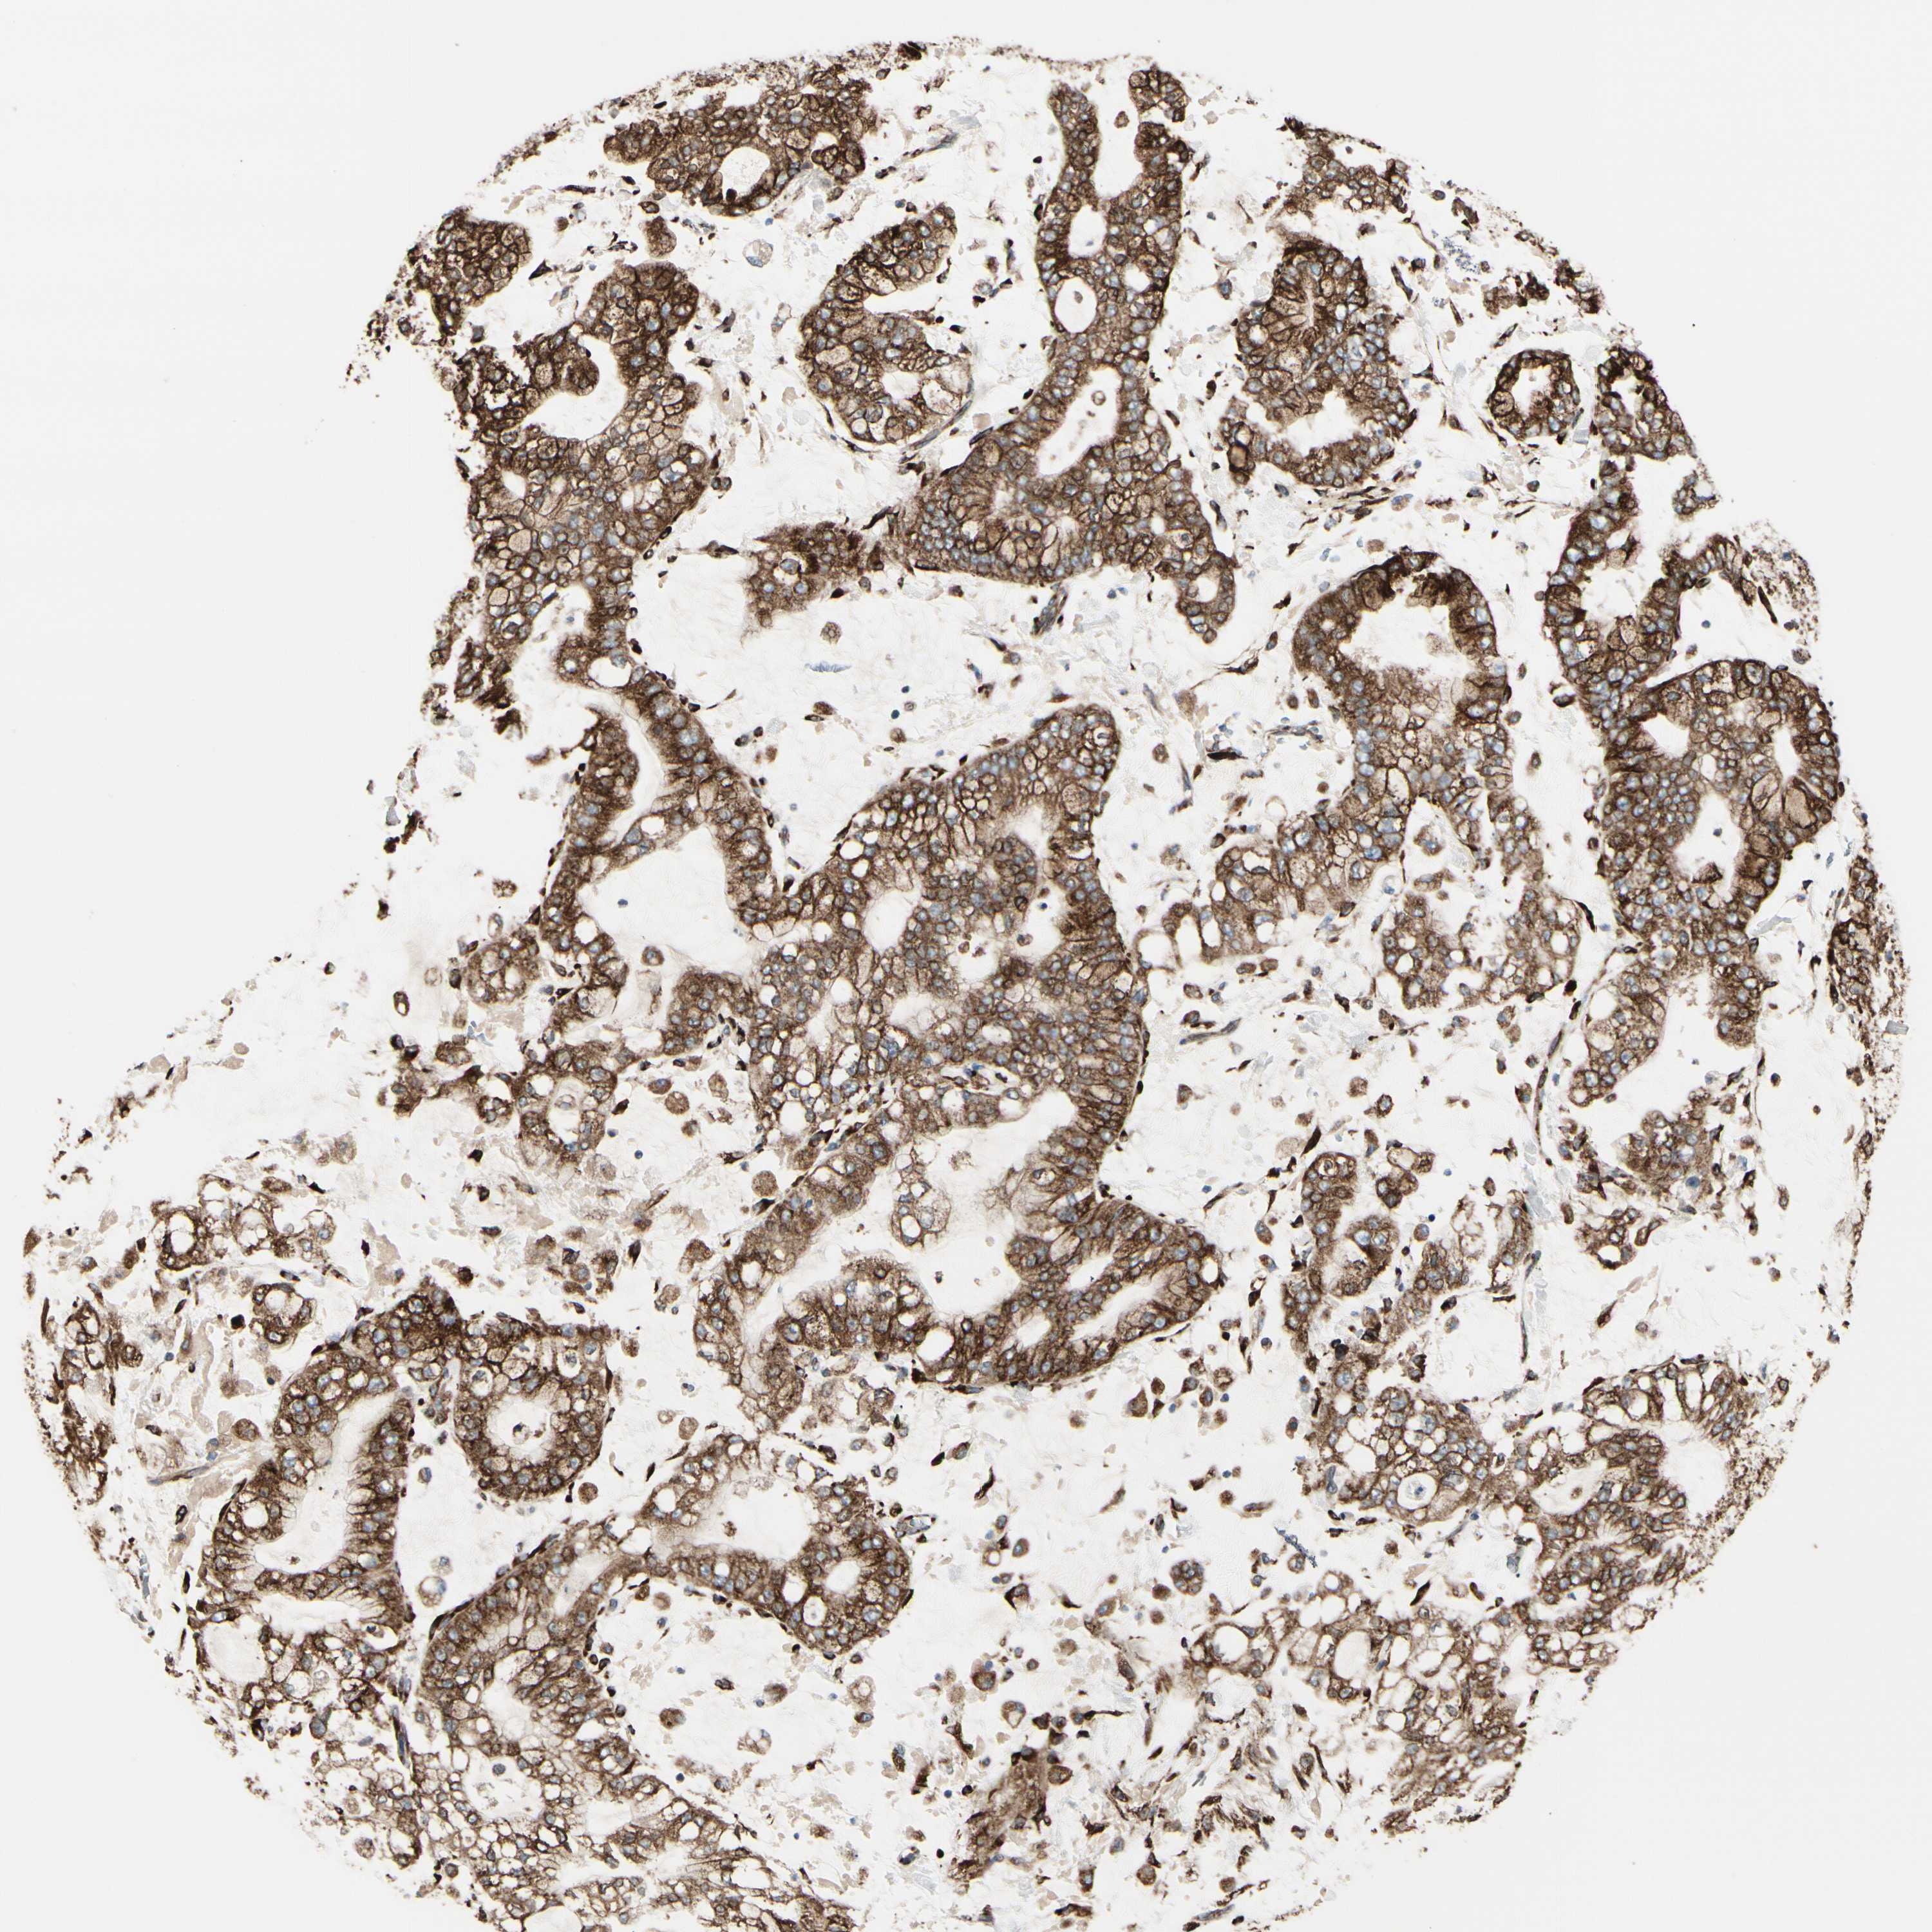

STOMACH CANCER - Protein expressioni

A mouse-over function shows sample information and annotation data. Click on an image to view it in a full screen mode. Samples can be filtered based on level of antibody staining by selecting one or several of the following categories: high, medium, low and not detected. The assay and annotation is described here.

Note that samples used for immunohistochemistry by the Human Protein Atlas do not correspond to samples in the TCGA dataset.

Antibody stainingi

Antibody staining in the annotated cell types in the current human tissue is reported as not detected, low, medium, or high, based on conventional immunohistochemistry profiling in selected tissues. This score is based on the combination of the staining intensity and fraction of stained cells.

Each image is clickable and will lead to virtual microscopy that enables deeper exploration of all samples and also displays staining intensity scores, fraction scores and subcellular localization as well as patient and tissue information for each sample.

Antibody HPA009026

Antibody HPA011924

Staining

High

Medium

Low

Not detected

Intensity

Strong

Moderate

Weak

Negative

Quantity

>75%

75%-25%

<25%

None

Location

Nuclear

Cytoplasmic/membranous

Cytoplasmic/membranous,nuclear

Adenocarcinoma, NOS

Adenocarcinoma, High grade